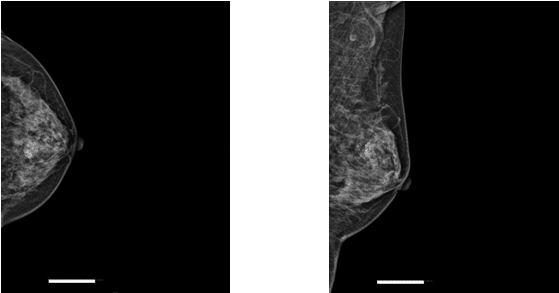

乳腺钼靶检查:乳腺早期病变的敏锐“侦察兵”

乳腺钼靶检查,堪称乳腺健康的忠诚“守门员”。通过对比影像资料,它能够敏锐地发现乳腺内的微小钙化点和肿块,对早期乳腺癌的筛查具有极高的价值。

早期发现:它就像一双敏锐的眼睛,能够探测到直径小于 1 厘米的肿瘤,对致密性乳腺中乳腺癌特异性钙化极为敏感,为乳腺癌的早期诊断立下汗马功劳。

适用广泛:尤其适合 40 岁以上女性的常规筛查,乳腺癌高风险人群也能通过它及时发现潜在隐患,做到防患于未然。

经济简便:价格亲民,检查过程快捷,通常几分钟就能完成,不会给您的生活和工作带来过多负担。建议大家在月经结束一周后进行检查,以获得更准确的结果。